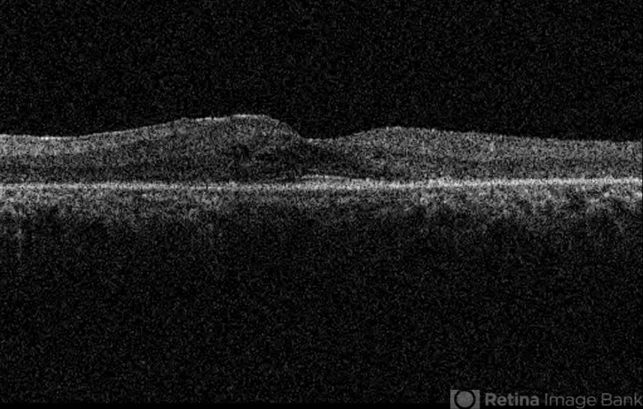

- cystoid macular edema (CME), retinitis pigmentosa, optical coherence tomography (OCT)

- Elham Salehi, Negah Eye Center, Tehran

- Topcon OCT

- OCT image of the left eye of a 30-year-old woman with cystoid macualr edema due to retinitis pigmentosa.